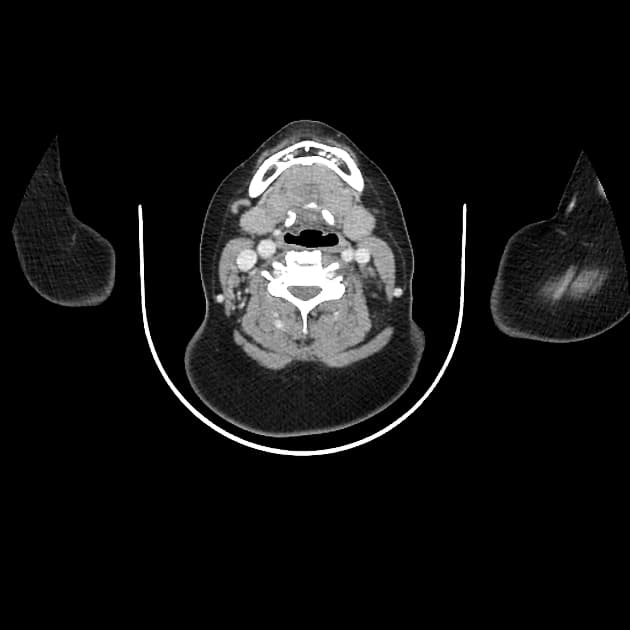

Chụp cắt lớp vi tính mạch máu động mạch chủ ngực (CT Angiogram Thoracic Aorta):

Chụp có cản quang pha động mạch (sử dụng Omnipaque 350). Không có hình ảnh cắt lớp trước đây để so sánh.

Không thấy tổn thương động mạch chủ do chấn thương hoặc máu tụ trung thất. Ghi nhận thấy ống động mạch còn thông (patent ductus arteriosus).

Ghi nhận tổ chức tuyến ức còn sót (remnant thymic tissue).

Ống động mạch (ductus arteriosus) là một mạch máu nối động mạch chủ xuống gần đoạn đầu với phần trần của thân động mạch phổi gần nơi xuất phát của động mạch phổi trái. Bình thường, ống này tự đóng trong vòng 24–48 giờ sau sinh do tăng áp lực oxy và giảm nồng độ prostaglandin. Việc không đóng lại sẽ dẫn đến tình trạng ống động mạch còn thông (patent ductus arteriosus – PDA).

Trong bối cảnh chấn thương, việc phân biệt giữa PDA và tổn thương động mạch chủ do chấn thương là rất quan trọng. Trong trường hợp này, vị trí giải phẫu, không có bất thường thành mạch, cùng với việc không có máu tụ trung thất hoặc các tổn thương ngực đáng kể khác giúp khẳng định chẩn đoán PDA.